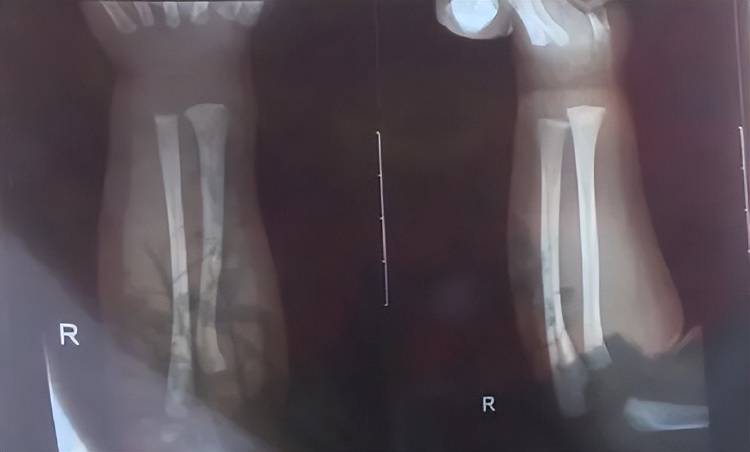

次日上午,孩子被带到附近医院检查,医生诊断发现他右手有两处骨折,第一处为右侧尺骨远端骨折,第二处为右侧桡骨远端骨折,随后医生给他做了石膏固定,“没想到,几天后孩子还被诊断出脑电图异常,医生建议复查。”

孩子被诊断发现两处骨折